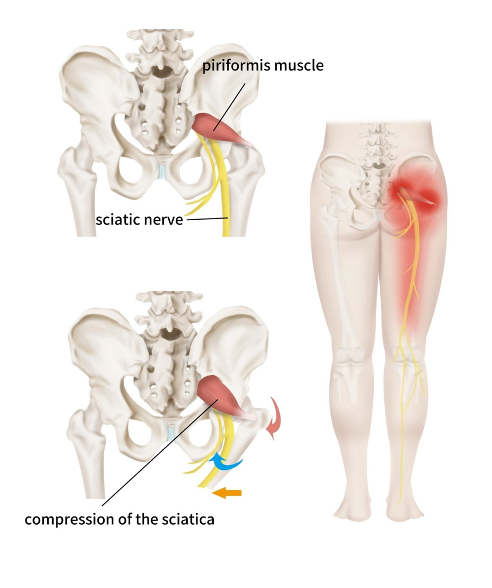

คือภาวะที่กล้ามเนื้อ Piriformis ซึ่งอยู่ลึกบริเวณสะโพก เกิดการตึงหรืออักเสบ กล้ามเนื้อนี้อยู่ใกล้กับ เส้นประสาทไซอาติก (Sciatic nerve) ซึ่งเป็นเส้นประสาทเส้นใหญ่ที่วิ่งจากหลังส่วนล่าง ผ่านสะโพก ลงไปถึงขา เมื่อกล้ามเนื้อบริเวณนี้ตึงหรือเกร็งมากเกินไป

*อาจไป กดทับเส้นประสาท ทำให้เกิดอาการปวดหรือชาร้าวลงขาได้

เมื่อกล้ามเนื้อสะโพกทำงานหนักเกินไป จะทำให้เกิด การตึงสะสม จนกดทับเส้นประสาท และเกิดอาการปวดร้าวลงขาได้